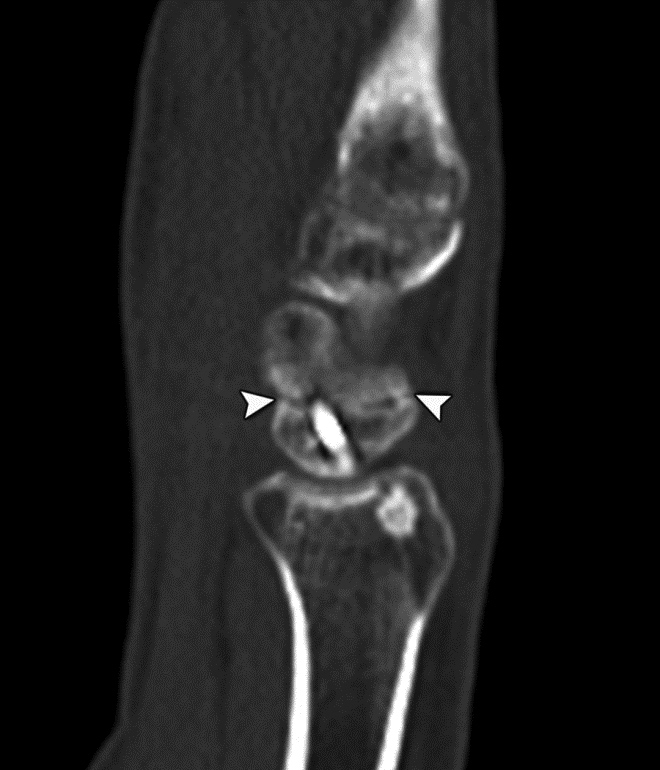

Scaphoid Fracture Evaluation. (A) Sagittal multiplanar reformation shows central portion of compression screw in the scaphoid with incomplete union at periphery of fracture site (arrowheads). Note absence of streak artifact due to small size of screw. (B) Coronal multiplanar reformation shows fracture union at the central portion of the scaphoid waist, indicating partial union.